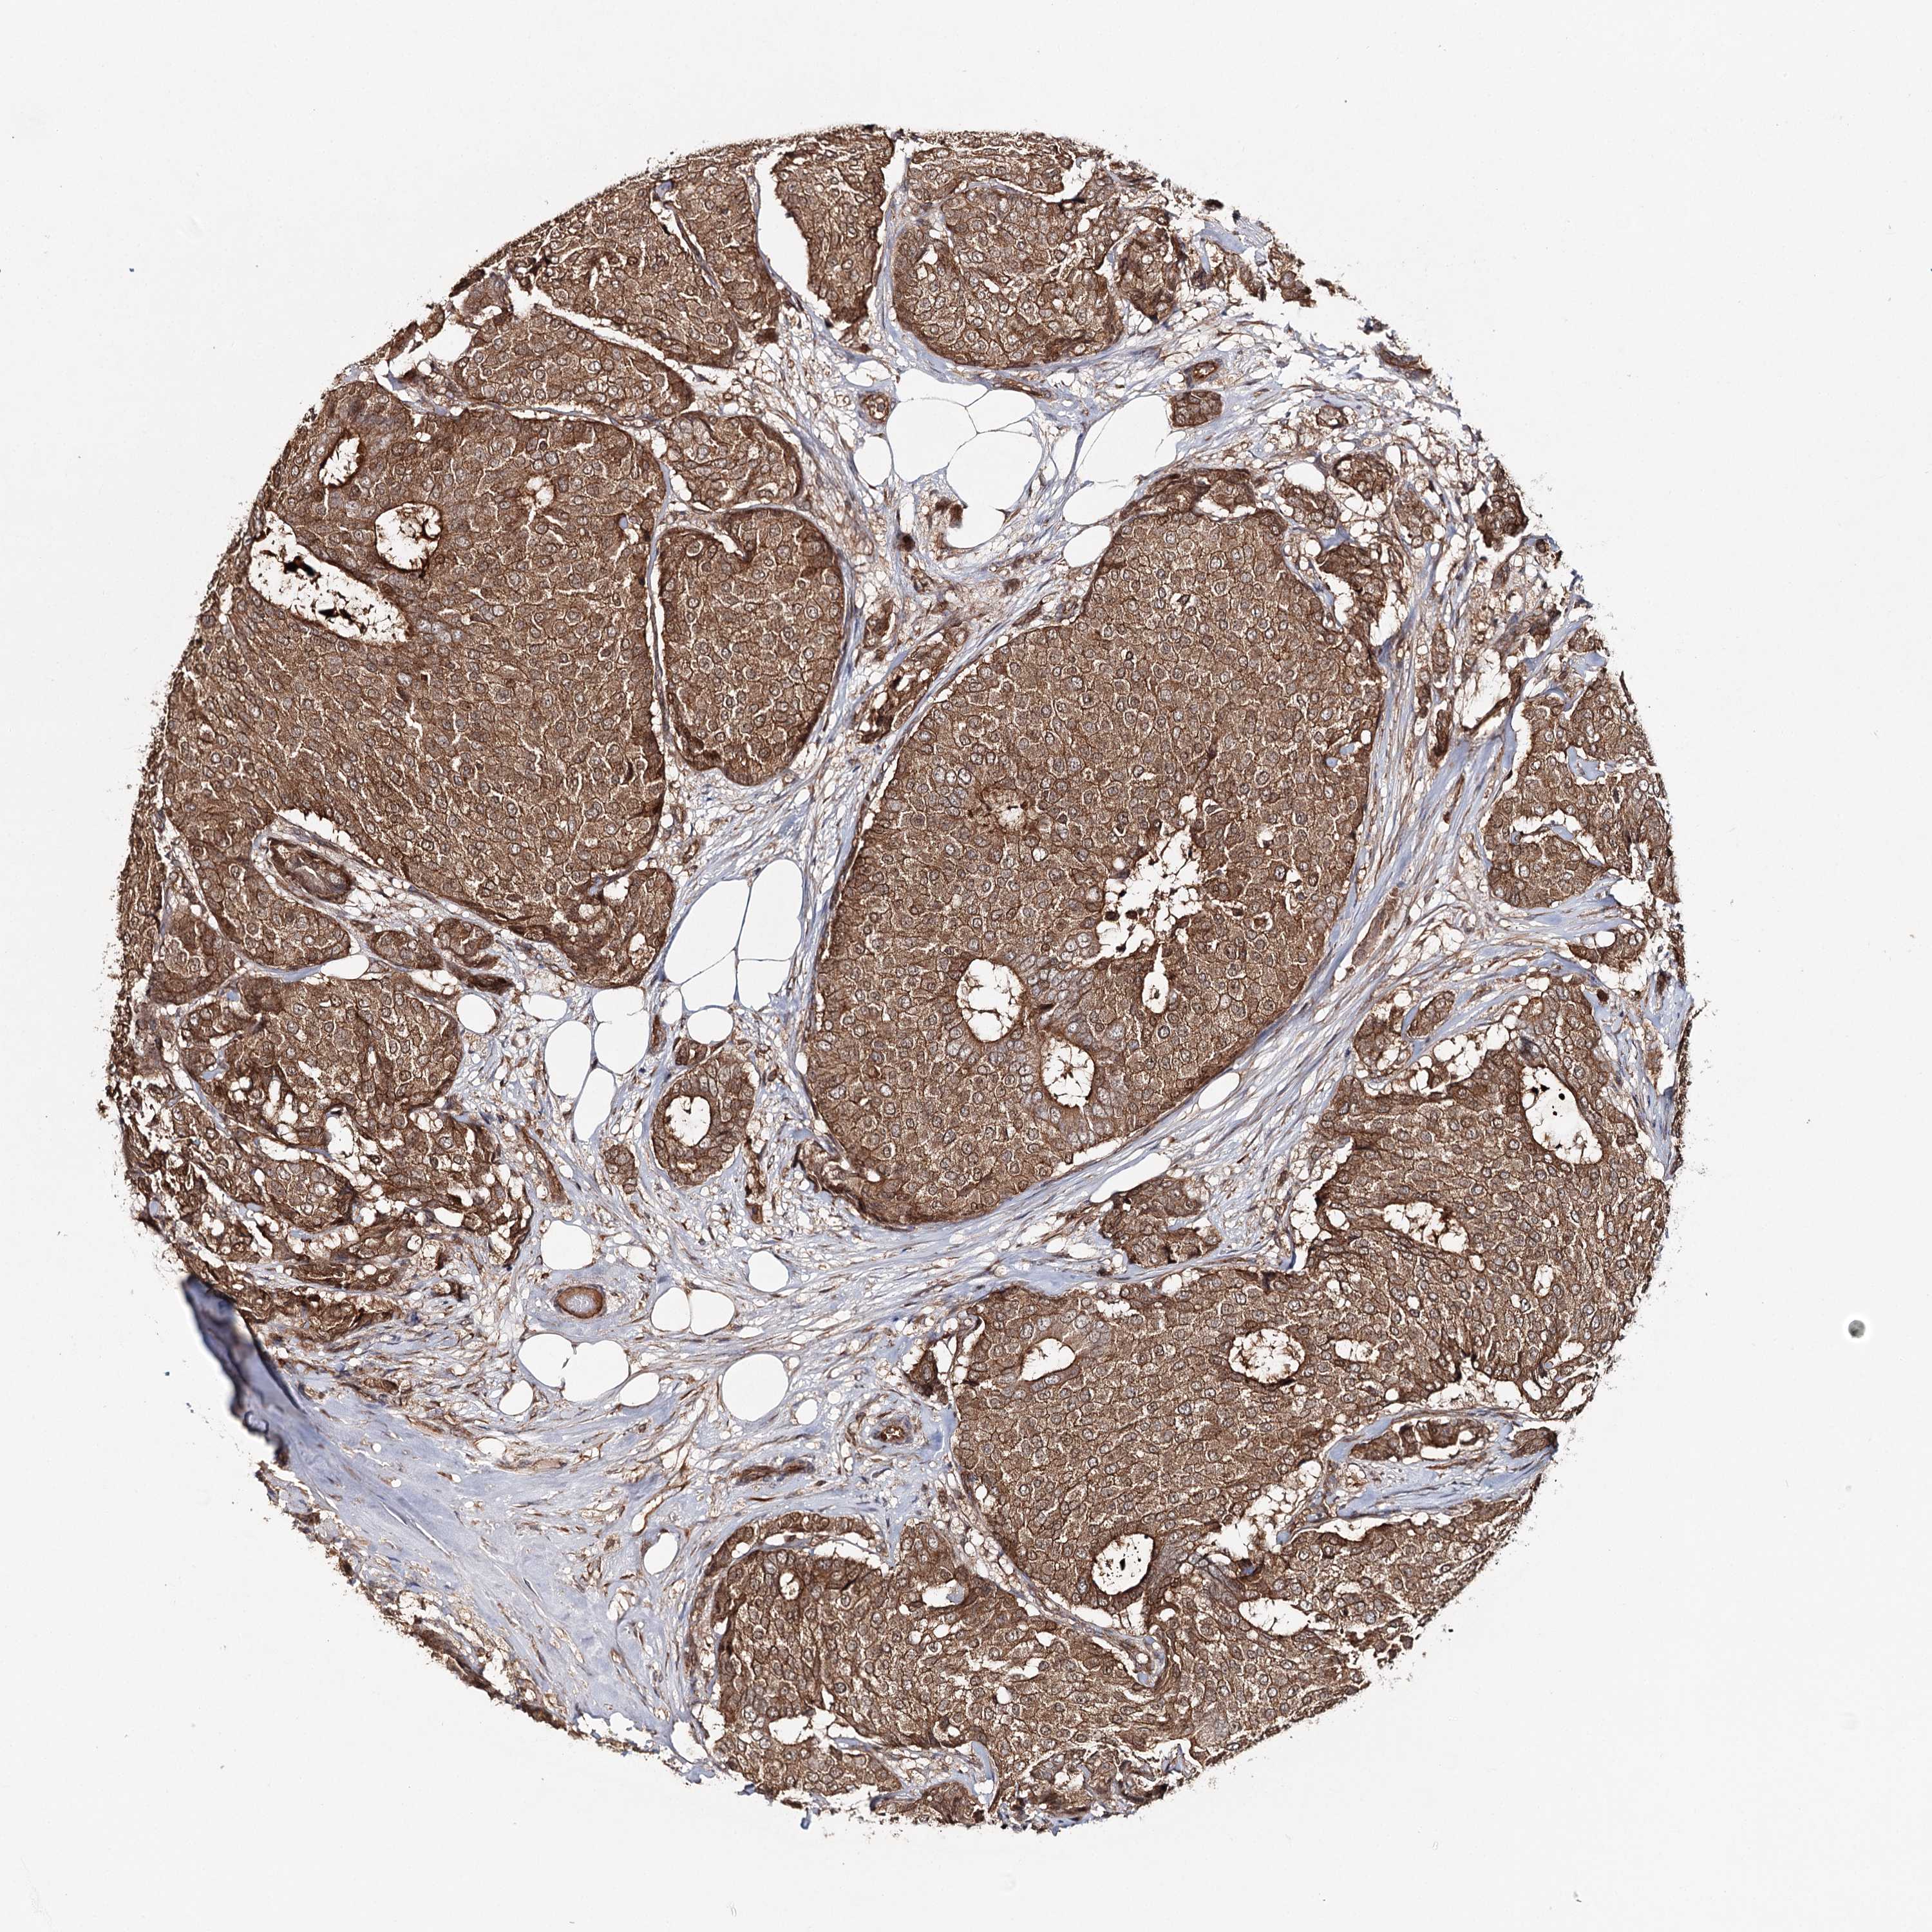

CANCER BREAST CANCER Show tissue menu

Breast cancer

Human cancer